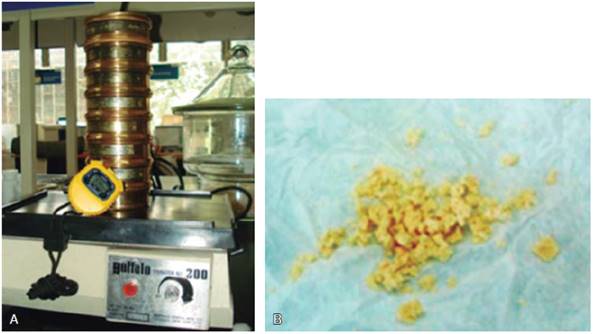

El DM fue a través de la determinación del tamaño medio de partícula (TMP) de tabletas masticadas elaboradas con Optocal modificado y a través del tamizaje volumétrico.6,13-16,24 Para ello, se colocó al paciente en posición fisiológica de descanso sentado en un banco frente al operador. Se le dio como instrucción masticar el alimento artificial en las cantidades indicadas en la prueba6,9 de forma habitual 40 ciclos masticatorios, tomando el tiempo. Inmediatamente escupieron dentro de un papel filtro todos los fragmentos de la boca, enjuagándose con agua para recuperar remanentes y enjuagando sus dentaduras, además, se examinó la cavidad bucal para verificar que no quedaran partículas remanentes. Este procedimiento se repitió un total de seis veces, la primera muestra fue desechada, ya que sólo se realizaba como prueba de familiarización. Cada muestra fue enjuagada y desecada en una cámara por medio de perlas de sílica durante 24 horas. Después fue colocada dentro de la torre de siete tamices (apertura de malla de 5.6, 4.0, 2.8, 2.0, 0.85, 0.425 y 0.25 mm) sobre un vibrador dental durante dos minutos. El material en cada tamiz era pesado en la báscula de precisión de 0.01 g OHAUS® (Figura 5), y se calculaba el TMP por medio de la ecuación de Rosin-Rammler (Qw = 100 [1 - 2-(x/x50)b]).25

Fuente directa.

Figura 5 A) Equipo para calcular la distribución del alimento artificial en mallas de diferente tamaño. B) Tabletas masticadas durante 40 ciclos masticatorios.